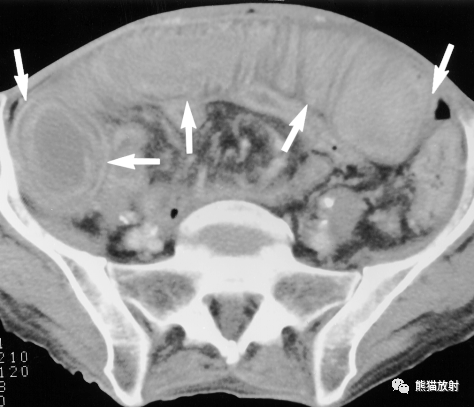

假膜性结肠炎。整个结肠壁明显增厚(厚度15mm)和结肠周围炎性改变。横结肠的增厚是不对称的。

假膜性结肠炎。整个结肠壁明显增厚,密度减低,提示水肿或炎症,结肠黏膜因充血而强化明显。可见结肠周围炎症和腹水。

假膜性结肠炎。手风琴征,整个结肠壁明显增厚,形成手风琴的外观。还有结肠周围炎症和腹水。